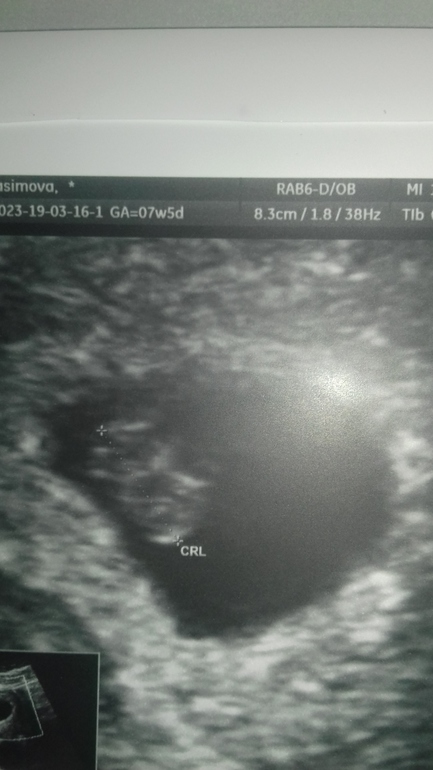

УЗИ, КТГ, доплерДевочки, кто опытный, успокойте и оцените. Сегодня в 3+5 эмбрионального и 5+5 акушерского сходила на первое узи. ПЯ в матке размером 12.2 на 11.3 мм, ЖМ 2.02 мм (На фото снизу). Это ок для такого срока?

У нас такие же размеры были в 5.5. В 7.5 послушали сердечко( в субботу). Все хорошо у вас. Про тонус не говорили ничего? Яйцо вытянутое немного.

на сроке 5.5

на сроке 7.5